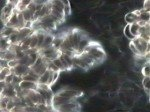

Live blood analysis involves visual examination of a small droplet of capillary blood from the fingertip. The blood is put on a glass slide and observed under a high-powered light microscope, typically dark-field. This method offers a qualitative visual perspective of the blood cells and plasma, known as the “biological terrain” in integrative healthcare, which supports and sustains the cells and their vitality.

You will be able to view the various components of your blood such as the size, shape, associations, ratios and fine structure of the red blood cells, various types of white blood cells, platelets and blood plasma, as they function in the body.